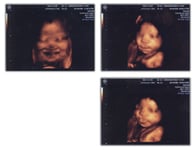

4D超音波胎児動映像システム 凹凸までよくわかる立体画像の最新4D超音波胎児動映像システムで早ければ4ヶ月頃からお腹の赤ちゃんの顔までよくわかります。(この写真では笑っている表情まではっきり!)